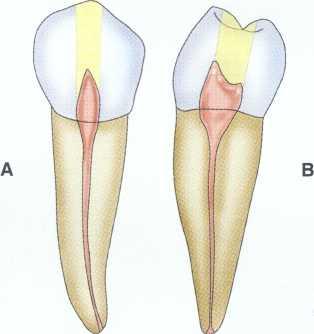

Unroo fing the Chamber

Unroofing the chamber and removing the coronal pulp facilitates the clinician's ability to visualize the chamber floor and aids in locating the canals. Complete removal of tissue and debris prevents discoloration and subsequent infection.

Unroofing the chamber and removing the coronal pulp (in vital cases) allow the clinician to see the pulpal floor. In cases of patent canals, most or all of the canal orifices may be easily located before the chamber is completely unroofed, but the clinician may nevertheless miss canals. In cases of calcification, performing these procedures increases the clinician's ability to visualize the pulpal floor and read the road map to the canal orifices detailed in the subtle color changes and patterns of calcification left by the receding pulp. This is extremely difficult or impossible to do through a "mouse hole" en-dodontic access.

Removal of the Coronal Pulp

Removal of the coronal pulp so that the canals may be located is necessary in cases with vital pulp. One advantage of removing the coronal pulp is that the radicular fragments may hemorrhage slightly, aiding in location of the canal orifices. This is especially useful in maxillary molar cases for locating the second mesiobuccal (MB2) canal.